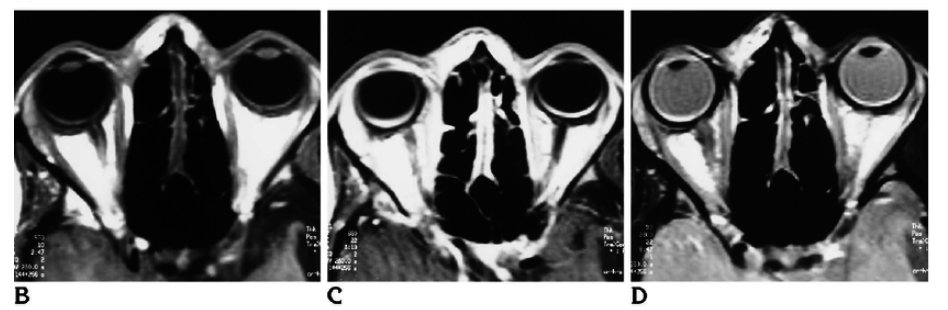

Bilateral Sturge-Weber syndrome. Postcontrast axial MR image ( A ) shows gross leptomeningeal thickening and enhancement related to the right hemisphere and less extensive abnormality of the left occipital region. Unenhanced axial T1-weighted image ( B ) shows thickening of the posterior globes bilaterally; after administration of contrast material ( C ), marked enhancement is seen in both globes. Abnormal high signal is present in this region on the proton density–weighted image ( D ). Bilateral, diffuse choroidal hemangiomas were found at ophthalmoscopy (not shown).